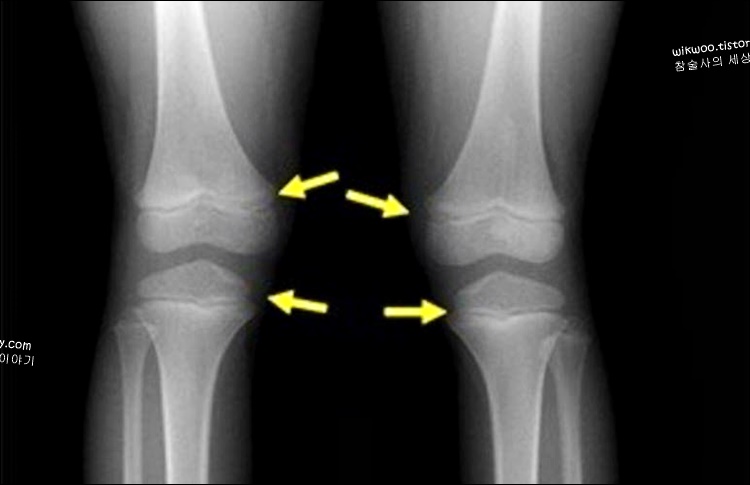

키가 큰다는 것은 뼈가 성장하고 있다는 것과 밀접한 관계가 있습니다. 연골로 형성되어 있는 성장판은 성장기에 있을 때 계속해서 연골이 증식되면서 키가 커지게 됩니다.

단 성장크리닉에서 X-RAY 검사를 한 결과 성장판이 닫혔다는 결과나 나왔다는 것은 뼈의 분화가 더 이상 쉽게 되지 않는다는 것을 의미합니다.

키성장은 성장판 부위 중에서 '무릎, 발목, 고관절'이 큰 영향을 끼치게 됩니다. 따라서 키가 크는 효과적인 운동은 무릎과 발목, 고관절의 성자판을 자극하는 운동이 가장 좋습니다.